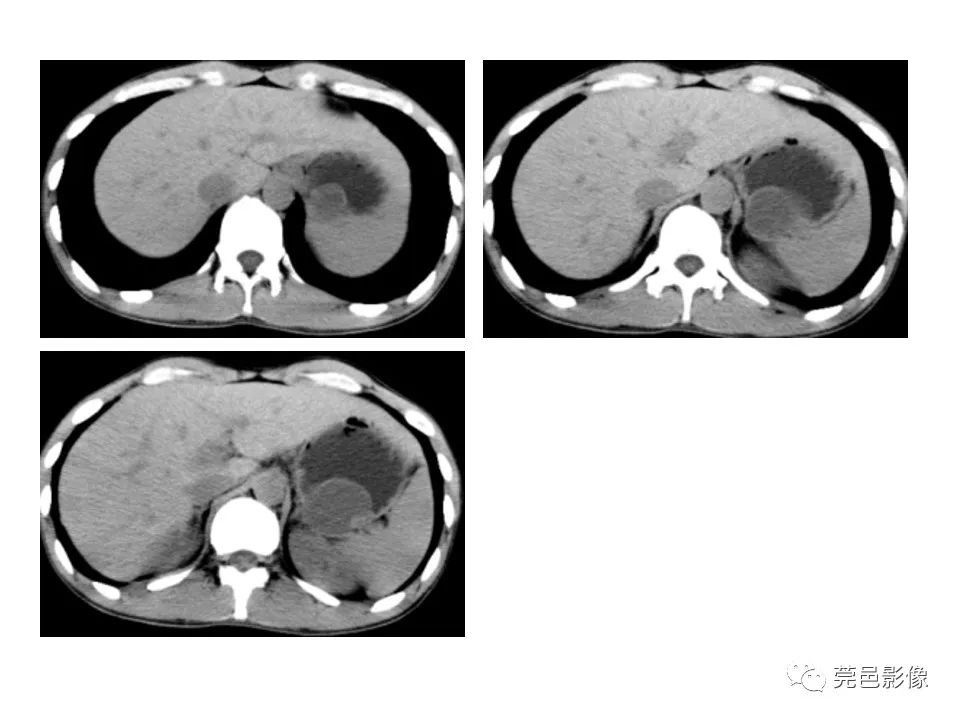

畸形|胃重复畸形CT诊断与鉴别诊断

【 畸形|胃重复畸形CT诊断与鉴别诊断】